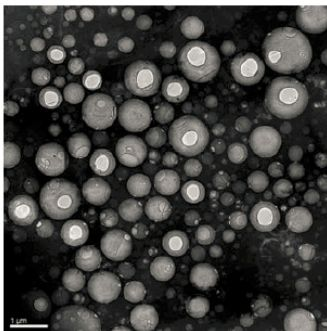

1.2壳层成分目前主流的超声造影剂壳层材料均以磷脂质为主,其优势在于磷脂质可以形成良好弹性的单层膜,保护微气泡能够在超声波发射中产生稳定振动,进而表现出优异的声学特性,增强超声成像效果。 1.3气体成分分析目前市售的超声造影剂产品多采用全氟碳化合物。相对于空气,全氟碳化合物具有较大的分子量、极低的水溶解度和缓慢的扩散速率;因此全氟碳化合物穿透磷脂膜的理论能垒较高。全氟碳化合物可以有效减缓微泡泄气速度,进而增强微泡的造影时间。USphereTM所使用的气体成分亦为全氟碳化物。二、 竞争产品比较与优势分析 常见的商用超声波造影剂有美系的OptisonTM(GE Healthcare)、Definity® (Lantheus Medical Imaging)、欧系的 SonoVueTM(Braco)和日系的SonazoidTM(GE Healthcare)。常见的商用造影剂比较表如表1。 优势1.UsphereTM较其他产品具有非常优异的粒径分布(如图2),它的微泡共振频率更适合用于目前医疗仪器的范围,大幅度提高超声信号的强度。其次,良好的粒径分布可以控制稳定穴蚀(Stable Cavitation)及惯性穴蚀(Inertial Cavitation)所致的生物效应,进而降低其在检测心血管疾病上的潜在风险和增强其在药物递送过程中的安全性。 优势2.UsphereTM系列产品粒径更小,在提供更为细致的成像品质的同时,仍保有在组织深部的回散射强度。 优势3.UsphereTM单位体积内的微泡浓度可达2.5x1010Bubbles/mL,为同类产品中浓度最高者。由于其粒径小、浓度高,对于肿瘤部位的血管造影更加明显。优势4.UsphereTM具有良好的稳定与悬浮特性(如图3),可以兼用作某些声学研究(如超声波场扫描与流体状态分析)。优势5.UsphereTM体内循环时间高达6-15分钟(如图4),利于活体实验。开封活化后三天可保持极高品质,方便活体实验。而目前市场占有率较高的SonoVueTM仅有6小时的开封后使用时间。 图2USphereTM的物理表征:

电子显微镜图(Cryo-TEM)

粒径分布图(Multisizer3,USPcompliant)

Figure 2. Characterization of USphereTM. Left:TEM (Cryo-TEM); Right: size distribution (Multisizer3,USP compliant)